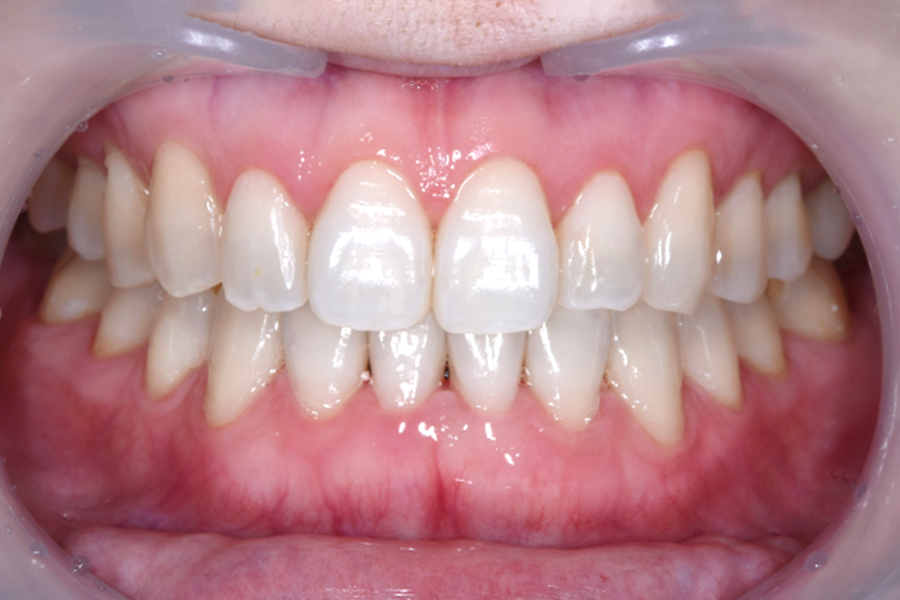

| 主訴 | 上下前歯のガタツキと口ボゴ、突出が気になる |

|---|---|

| 治療期間 | 2年2か月 |

| 治療費 | マウスピース矯正とホワイトニングセット 1,018,296円(税込) |

| 治療内容 | 目立ちにくいマウスピース矯正(非抜歯矯正) 歯と歯の間に隙間をつくることにより、歯列弓を広げながら治療を行いました。 また矯正用マウスピースをトレー代わりにし、ジェルを入れてホームホワイトニングを同時に行っております。 |

| 治療のリスク |

・後戻りする可能性があるのでリテーナーを最低でも矯正期間以上はつけること。 ・ホワイトニング後、一時的に痛みが出る場合があります。 ・稀にほっぺた、唇、舌などに口内炎や傷ができることがあります。 |